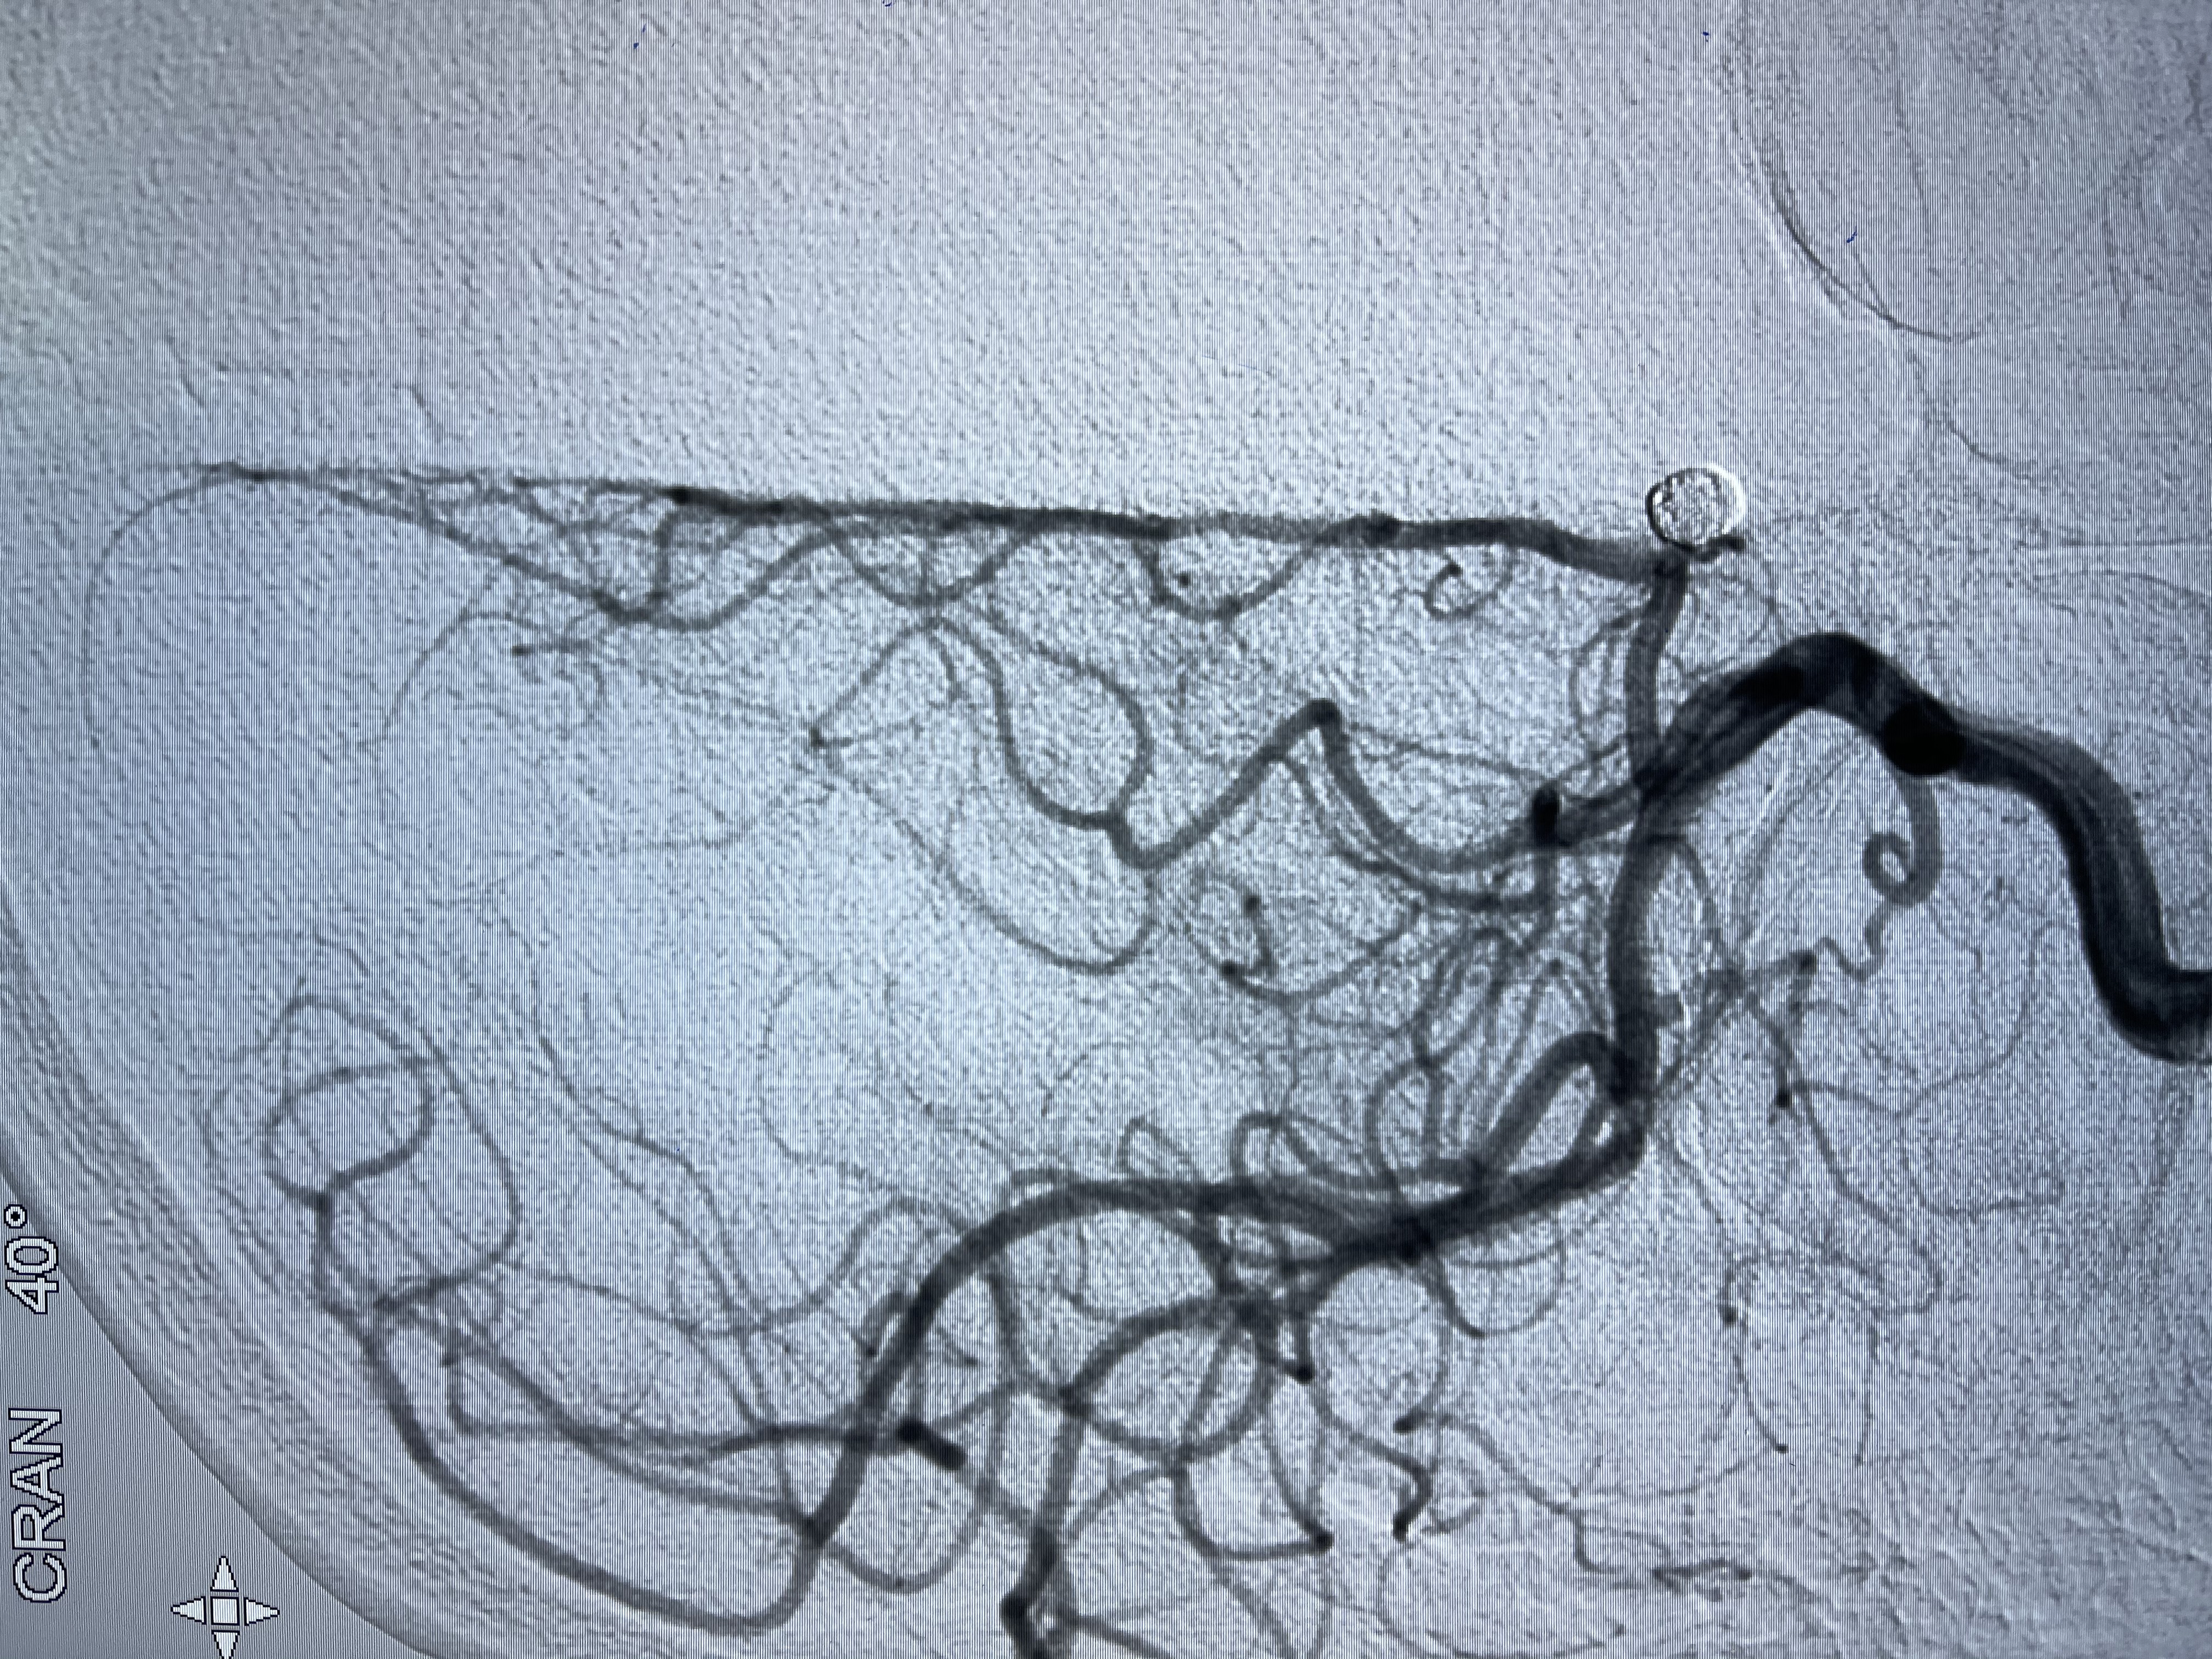

E10 45°角微导管塑形后轻松到位

5-15cm三维圈成篮:瘤颈部覆盖弹簧圈

3-6cm

2-6

2-6cm

微弹簧圈尾端弹出动脉瘤,栓塞微导管轻轻送入动脉瘤内

1-4cm

1-2cm

动脉瘤致密填塞